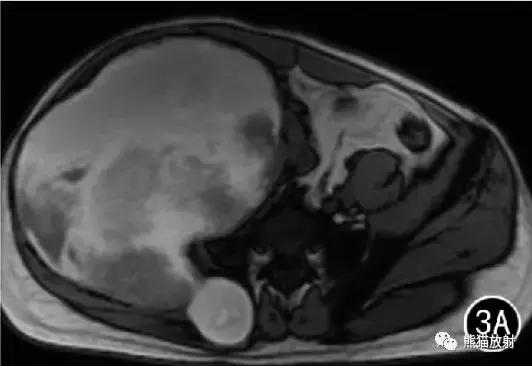

图3 男38岁。右侧髂骨骨内型假肿瘤。右侧髂骨区见巨大肿块,同髂骨翼骨质膨胀性破坏,邻近臀肌、髂腰肌及盆腔内组织受压移位,T1WI呈高、低混杂信号(A) ; 增强扫描未见强化。